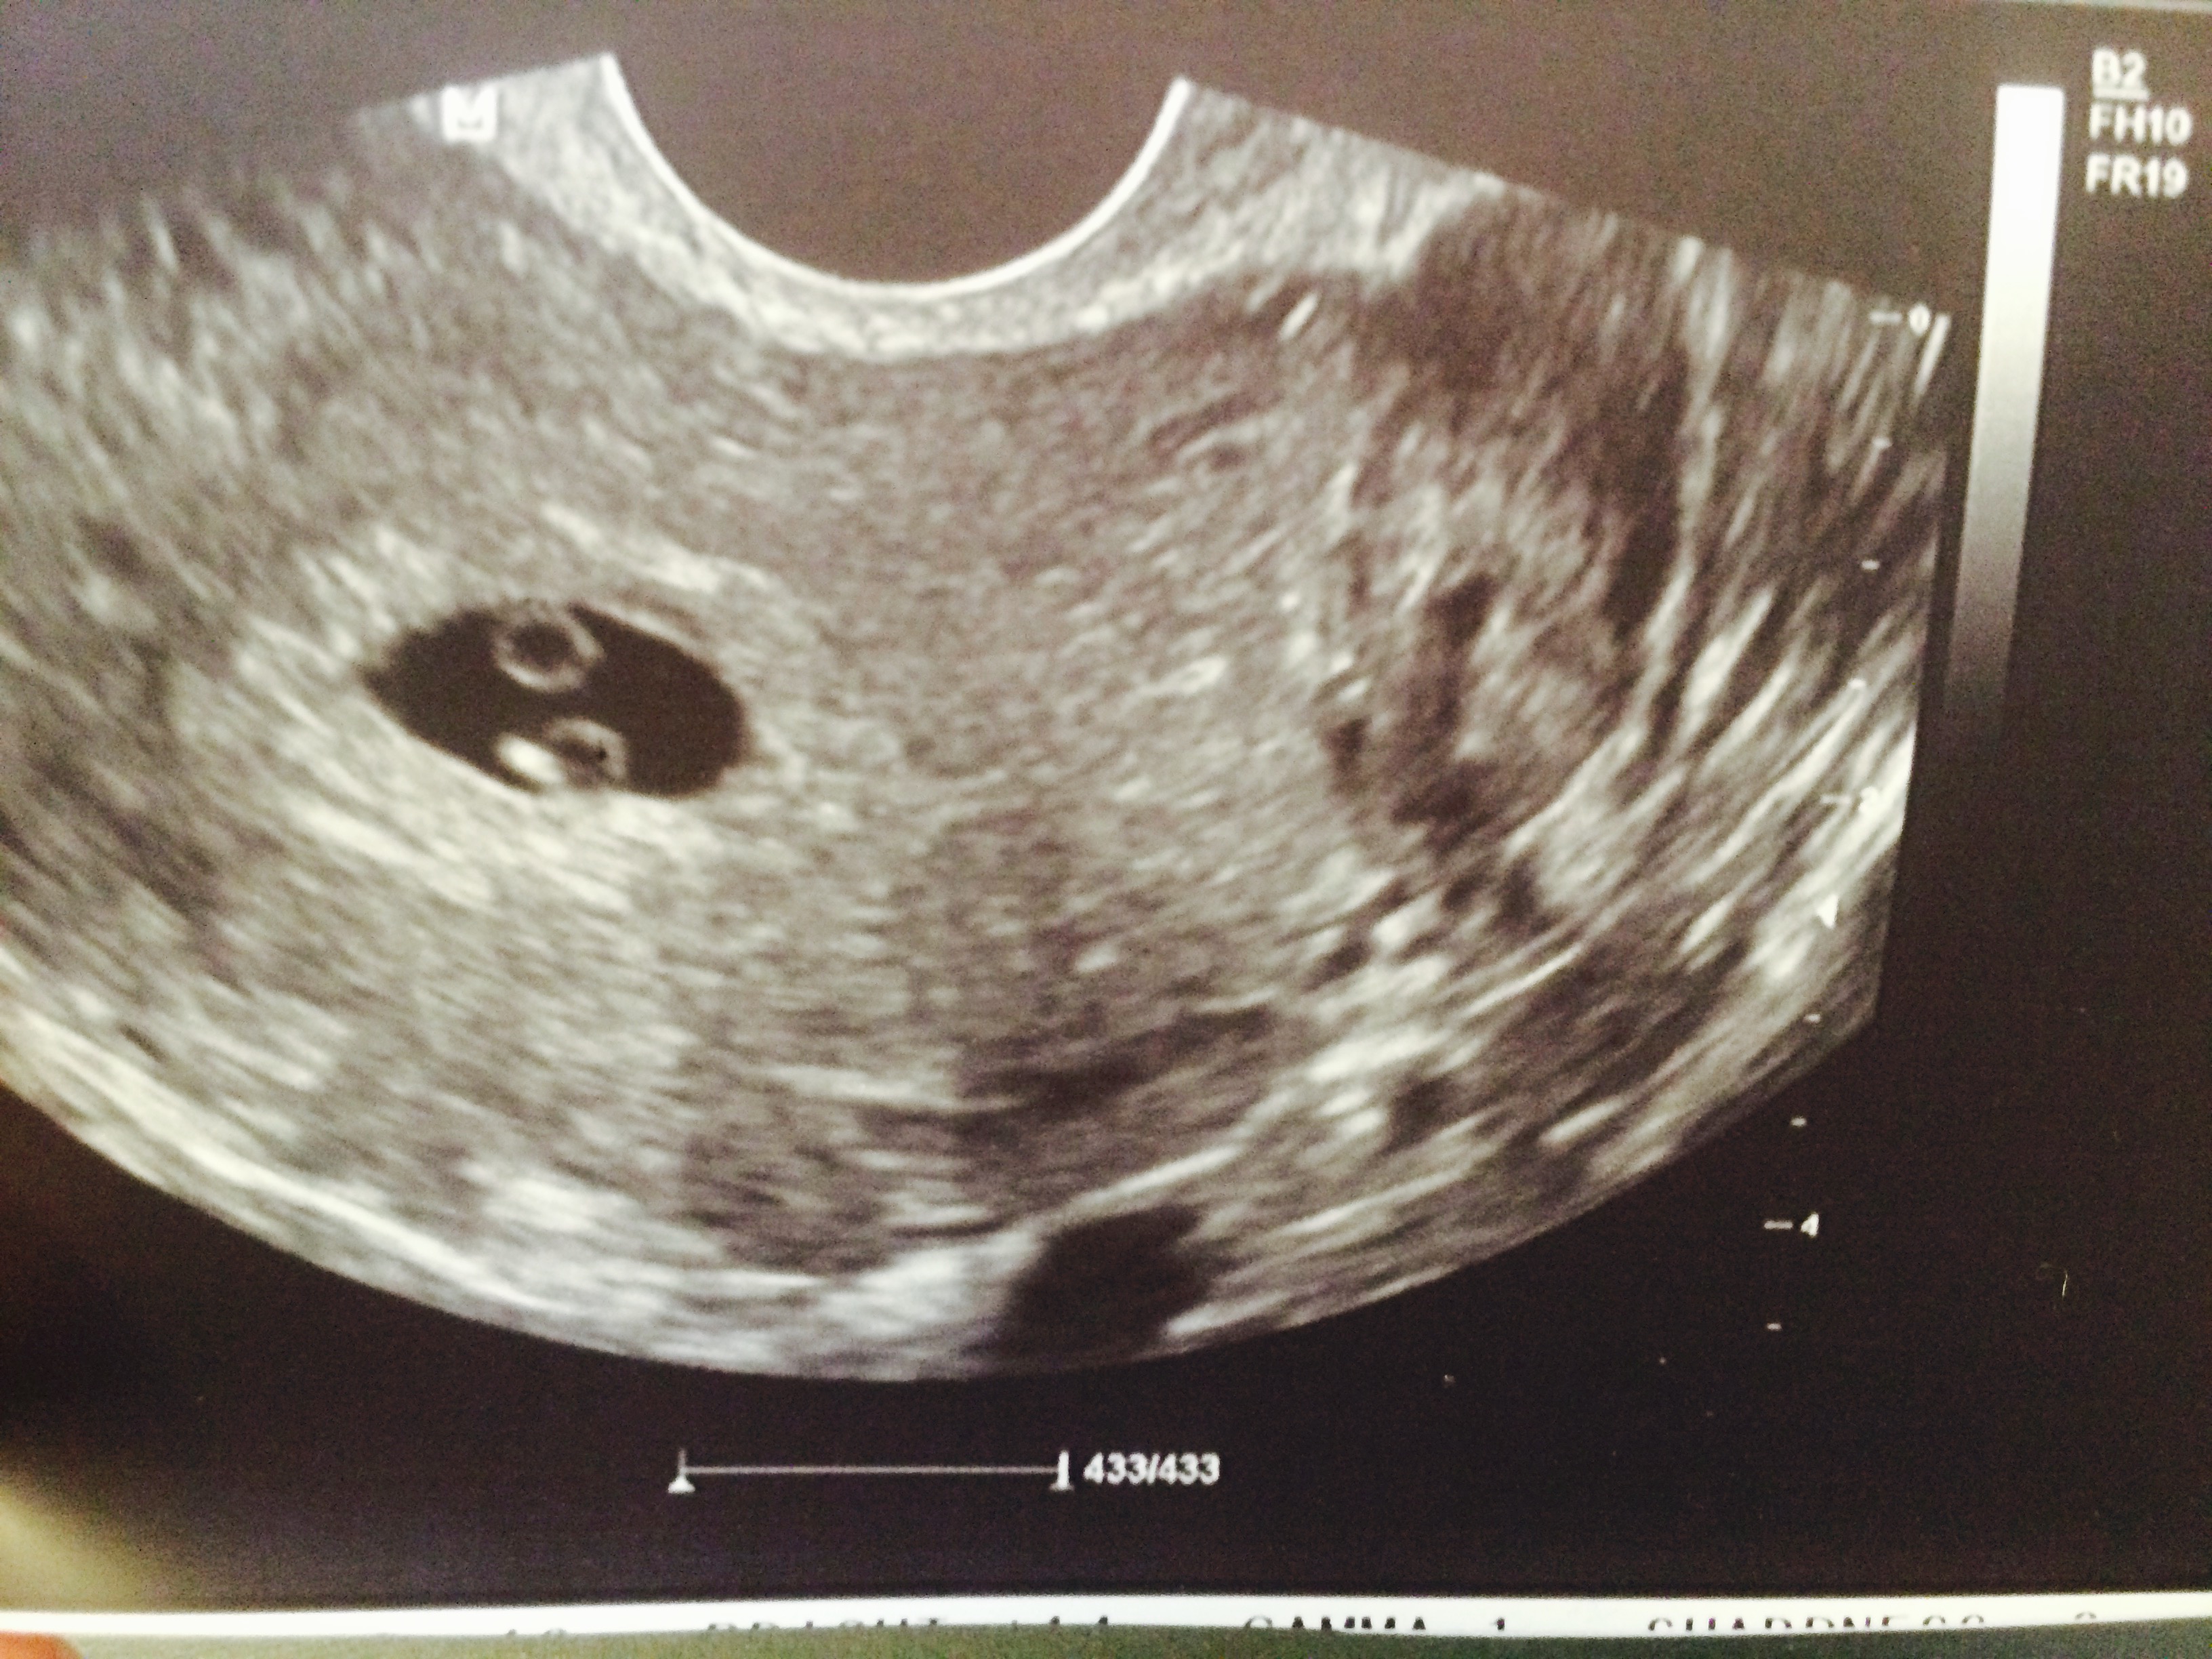

Got our first us on Mon! It was our dating us and baby was 6w6d about 2 days off from where I thought. Baby had a good heart beat (126bpm) but the pictures weren't really clear yet. So exciting to see!